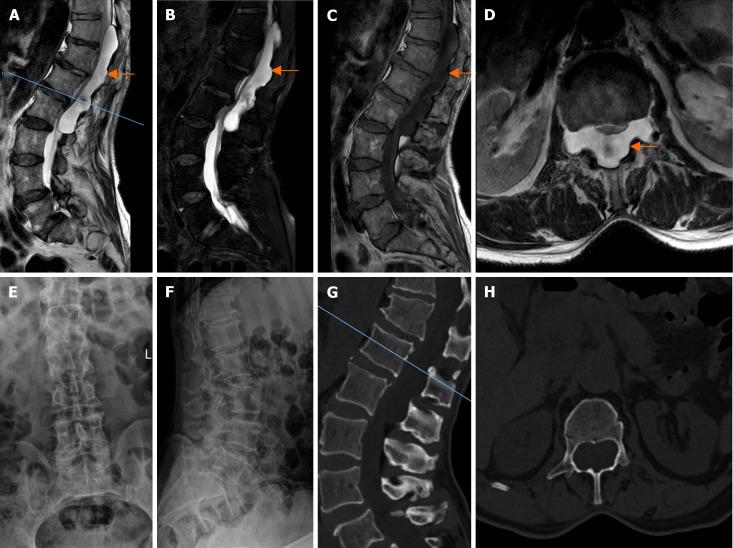

In July 2023, a 64-year-old male with a giant intravertebral epidural hemolymphangioma from thoracic 11 to lumbar 2 (T11-L2) was admitted to the Department of Spine Surgery at the People's Hospital of Binzhou City, China. The patient experienced progressive lumbar and left lower limb pain, numbness, weakness in both lower limbs, and difficulty with urination and defecation. Imaging studies revealed a large cystic mass in the spinal canal at T11-L2. Surgical decompression was performed, and the pathology confirmed hemolymphangioma.

2023年7月,一名64岁男性因胸11至腰2(T11-L2)巨大椎体内硬膜外淋巴管瘤入住中国滨州市人民医院脊柱外科。患者出现进行性腰痛、左下肢疼痛、双下肢麻木、无力以及排尿和排便困难。影像学检查显示T11-L2椎管内有一个巨大囊性肿块。进行了手术减压,病理证实为淋巴管瘤。